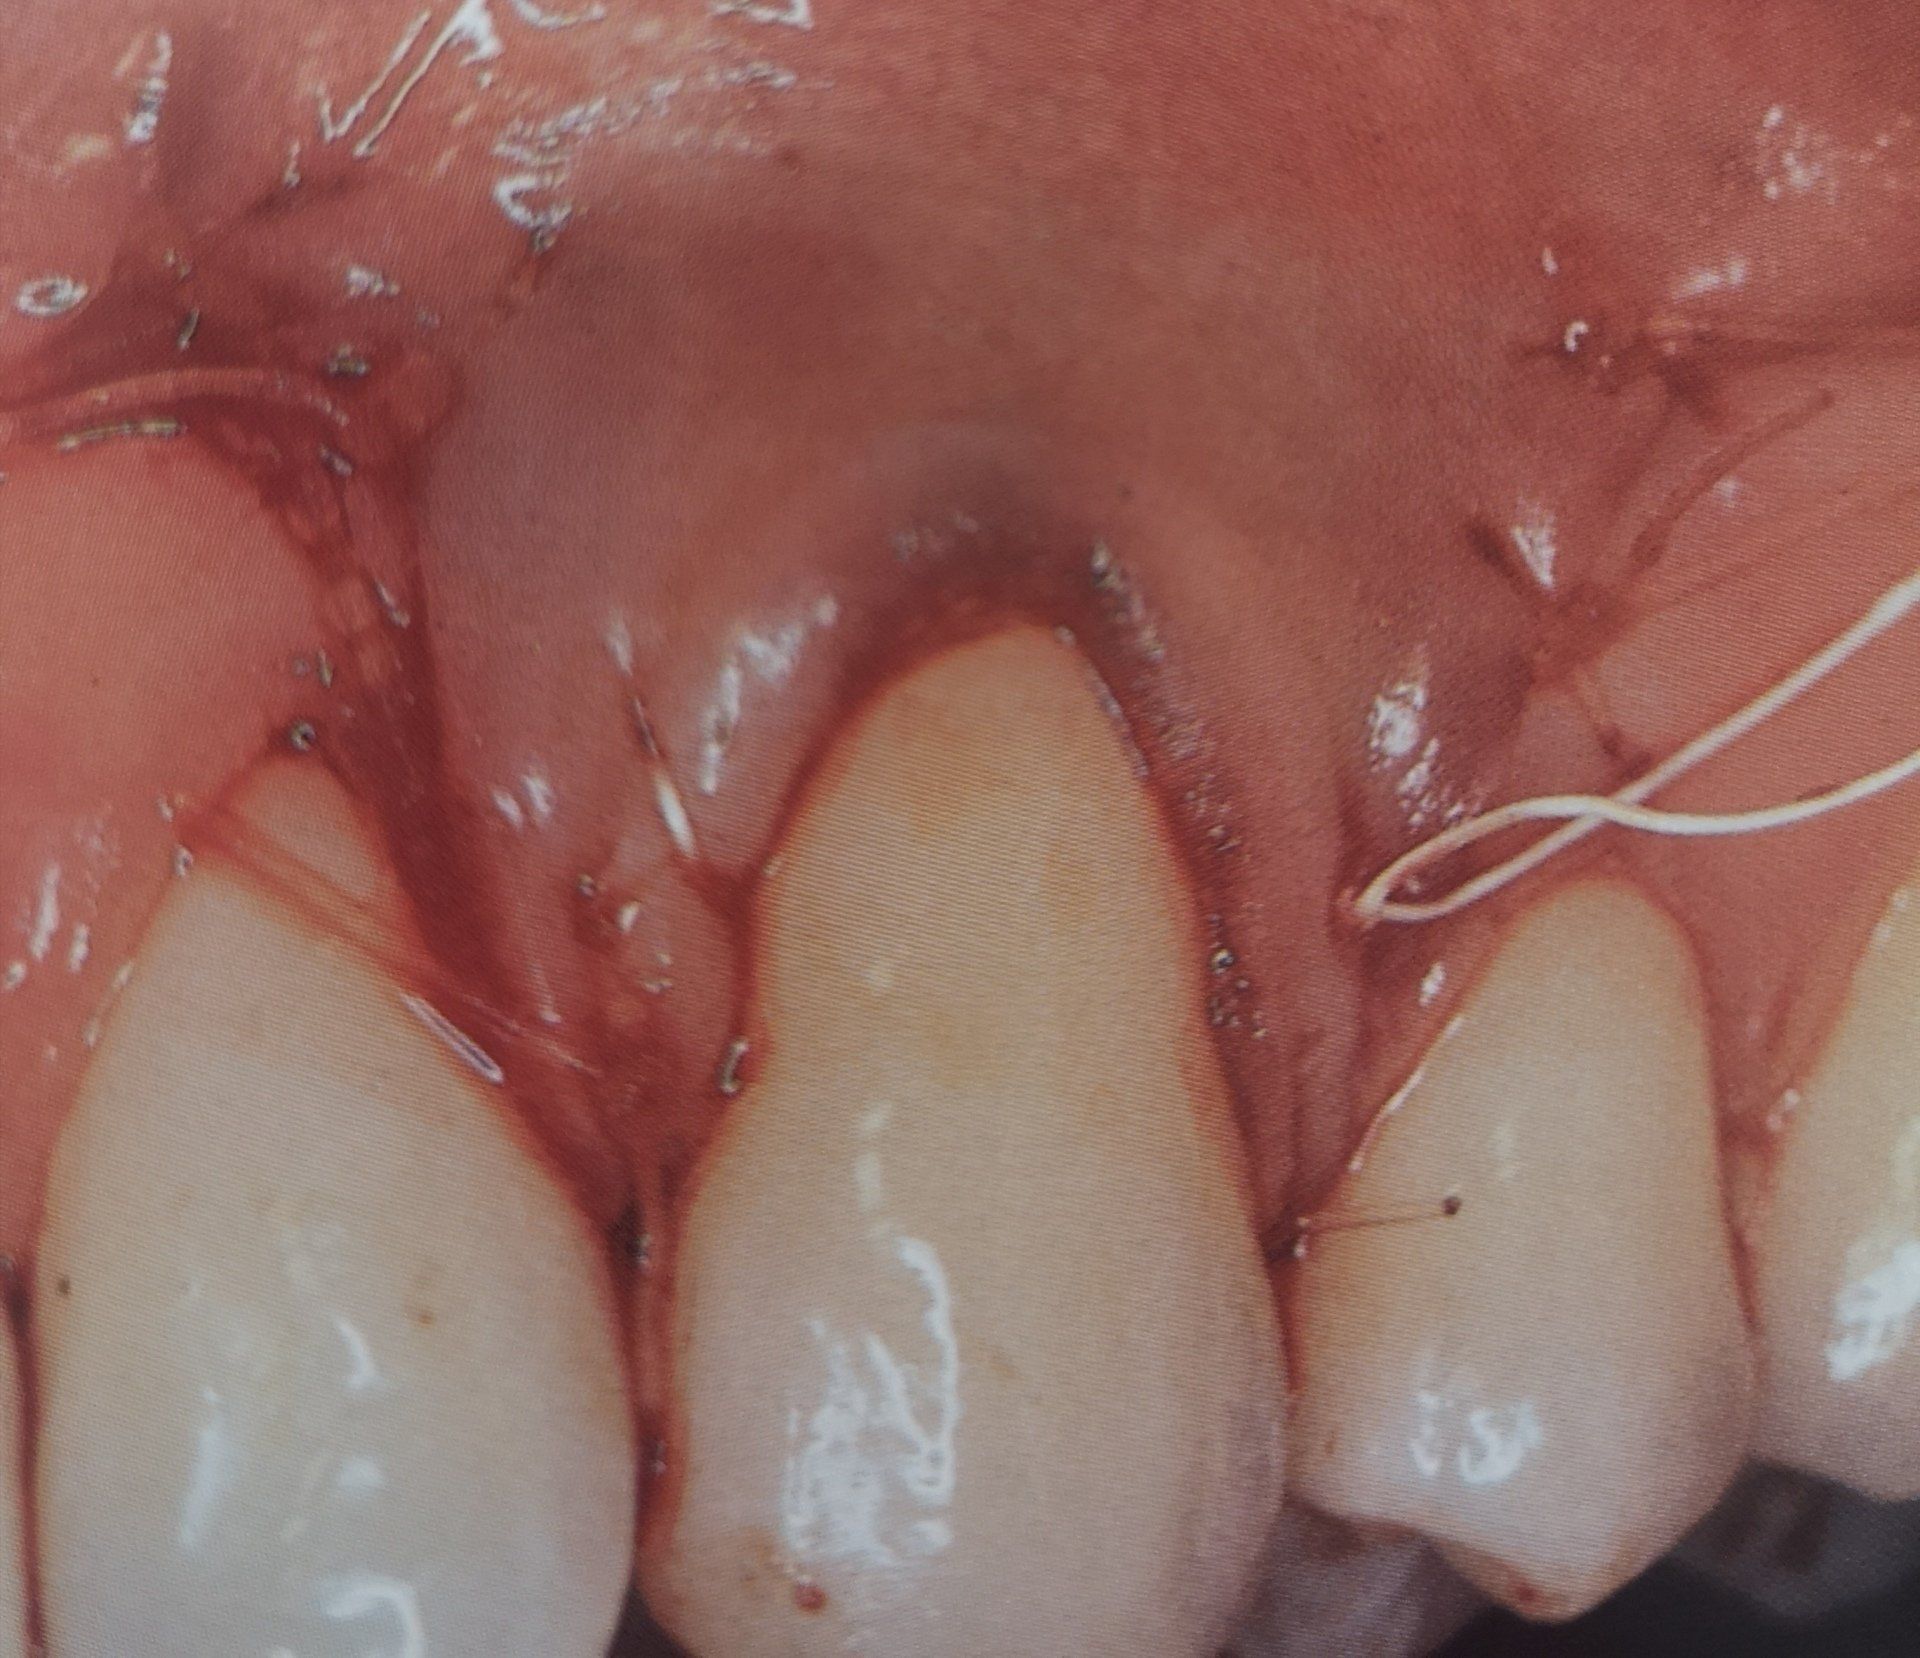

• Fasi iniziali: sedute di igiene orale professionale e courettage (pulizia profonda sotto gengiva) per rimuovere placca e tartaro;

• Fasi intermedie o avanzate: interventi di chirurgia parodontale rigenerativa o resettiva, che mirano a ripristinare i tessuti danneggiati e a ridurre le tasche parodontali;